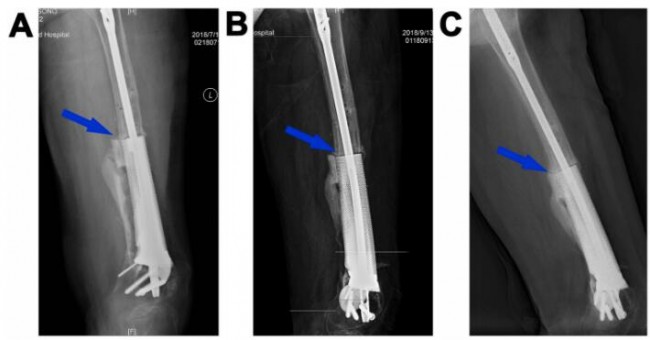

图5.3D打印多孔Ti6Al4V内植物重建股骨缺损(病例2)。末次术后即刻(A)和植入后2(B)、5个月(C)、8个月(D)、14个月(E)和20个月(F)重建的11cm股骨缺损的X线图像。蓝色箭头表示内植物和宿主骨之间的骨整合。